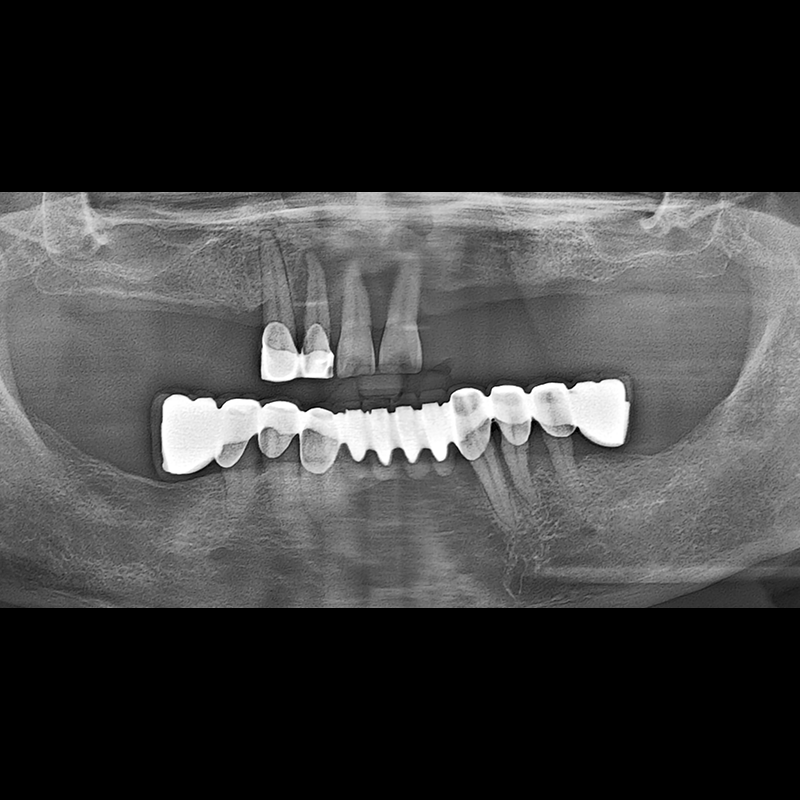

种植牙前后的照片 2025.05.30

在缺失的牙齿部分和难以挽救的牙齿位置植入了种植牙。